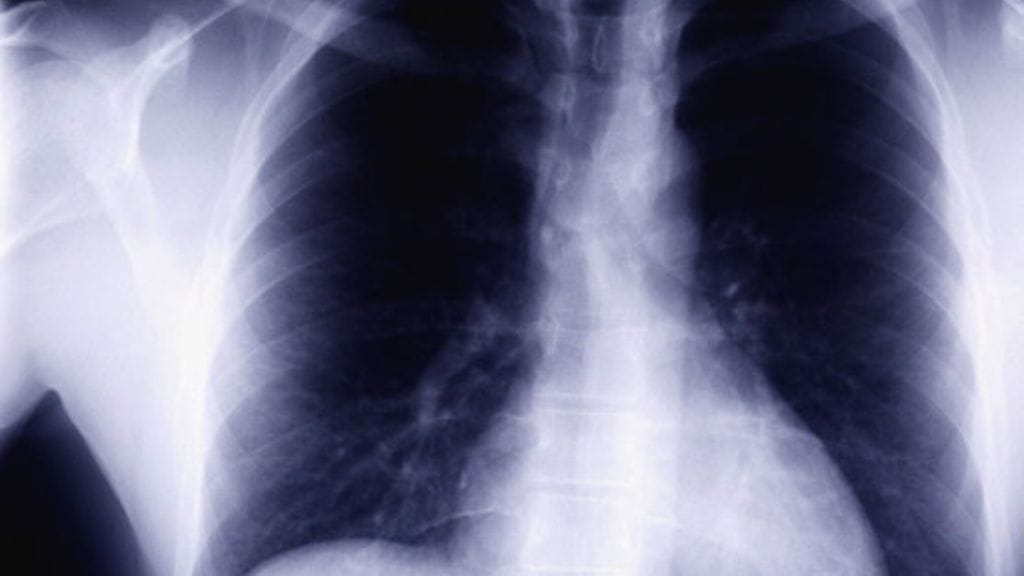

– Pyörryin yhtenä sunnuntaina lattialle ja heräsin ambulanssissa sireenien ulvontaan. Minut vietiin terveyskeskukseen, mutta suostuin keuhkokuvien ottoon vasta seuraavana päivänä.

– Oikea keuhko oli aivan ummessa ja vasenkin puoliksi. Kuvissa näkyi 2,4 cm x 4,1 cm syöpäkasvain.

– Kun heräsin, ympärilläni seisoi lääkäreitä, jotka pitelivät käsissään kolmen viikon takaisia ja juuri otettuja keuhkokuvia. He eivät olleet uskoa silmiään: keuhkoni olivat kuin parikymppisellä kollilla, ja syöpä oli poissa.

Kasvaimesta oli jäljellä vain 9 senttiä pitkä arpi.